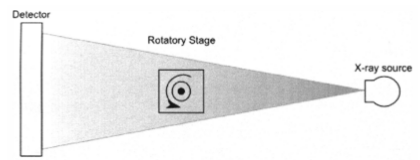

Se describe la implementación de un escáner micro-CT adecuado para ser utilizado como elemento complementario en

diferentes escáneres PET para pequeños animales. El diseño básico del sistema se basa en el montaje de un tubo micro-foco de rayos-X y un detector digital plano sobre un soporte rotatorio.

The goal of this work was the development of a low-cost micro-CT scanner, which could be used as an add-on in our previously developed PET systems for small-animals. The scanner design consists of a single-processor computer controlling a micro-focus X-ray tube and a flat panel detector, assembled in a common rotating gantry. The geometrical configuration was selected to achieve a spatial resolution of about 12 lp/mm with a field of view appropriate for small animals such as mice and rats. The radiated dose is controlled during the acquisition by two different elements: an aluminium filter and a tungsten shutter, attached to the X-ray source. The shutter is controlled by the computer in synchronism with the gantry rotation and the detector image integration.